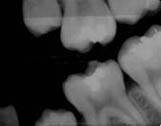

When all postmortem examinations have been done, comparisons between the ante- and postmortem examinations must be done. During this procedure it is of great value to have access to an identification program with a possibility to register all examinations. I have described this procedure in a foregoing message, by means of such a program a first matching of the ante- and postmortem examinations can be done. It is useful here to use an international program if several different countries are involved, and such a program has been constructed by means of the international police organisation-Interpol. Often, especially if there are only antemortem radiographs available, the same radiographs must be taken postmortem. In an example downunder you can see the antemortem radiograph to the left and the postmortem to the right.

Image 1Image 2

The victim in this case was a child, who was a passenger in a bus who crashed against a mountain side in Norway 1988. A very safe identification could be established by means of the radiographs. In fact, intraoral radiographs is one of the most accurate identification methods.